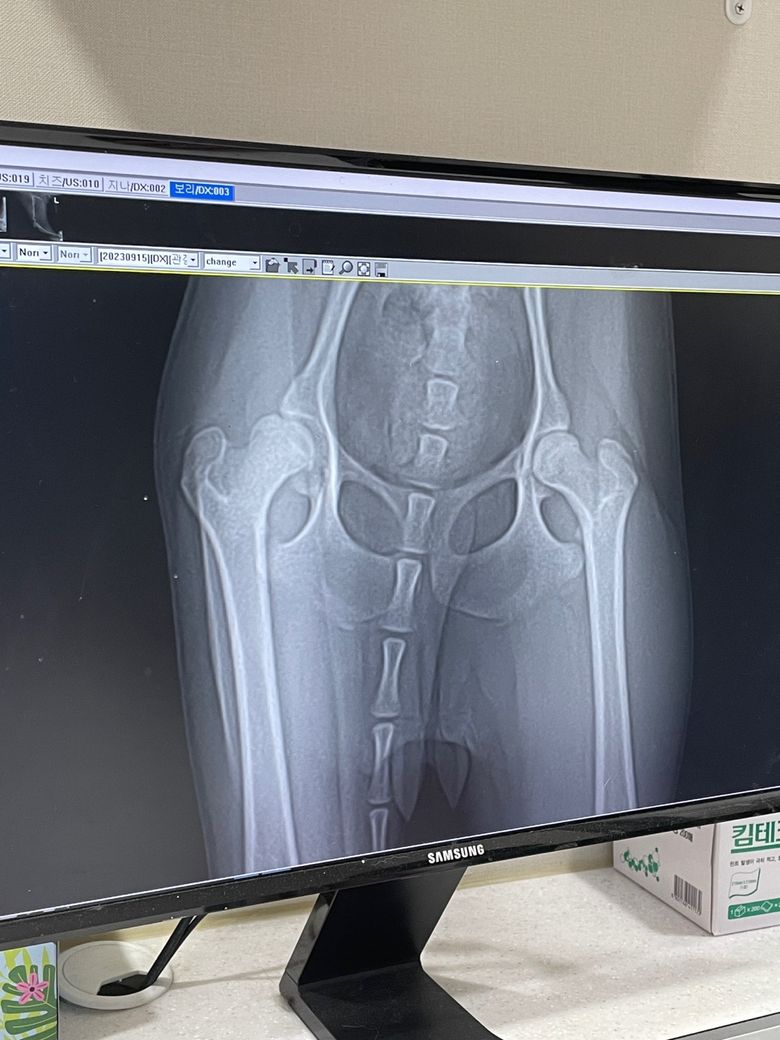

고관절 이형성증이 맞는지 ,엑스레이가 정확한건지 알수있을까요?

동물병원에서 엑스레이를 찍었는데 고관절 이형성증이라고합니다.

현재 강아지 상태는 왼쪽 다리만 써서 , 오른쪽 다리는 현재 근육이 아주 얇은 상태입니다.

이런건 물리치료나 주사치료 등으로 괜찮아 질수 없을까요? 빨리 수술을 해야하는건지 문의드립니다.

이 사진만으로 판단해서는 안되지만

시진상 확실한것은 대퇴골두의 관절면이 푹 패인듯한 양상의 병변이 보이고 있어 고관절 이형성증이나 OCD 등의 가능성을 강력히 고려해야 한다는 것입니다.

구조의 질환은 구조의 교정이 답이지 물리치료 등이나 약물로 해결되지 않습니다.

자전거바퀴가 휘어 있으면 펴주거나 교체하는게 답이지 구리스 좋은거 바르는게 답이 되지 못함과 같은 원리입니다.

고관절 이형성증은 고관절의 비구와 대퇴골두가 제대로 맞지 않아 관절이 불안정하거나 탈구되는 선천적인 질환입니다. 고관절 이형성증은 유전적, 환경적, 발달적 요인에 의해 발생할 수 있으며, 생후 6개월 미만의 강아지는 보조기나 석고 붕대를 사용하여 고관절을 안정화시키고 정상적인 발달을 도모하는 비수술적 치료를 시도할 수 있습니다. 생후 6개월 이상의 강아지는 보통 수술적 치료가 필요합니다.